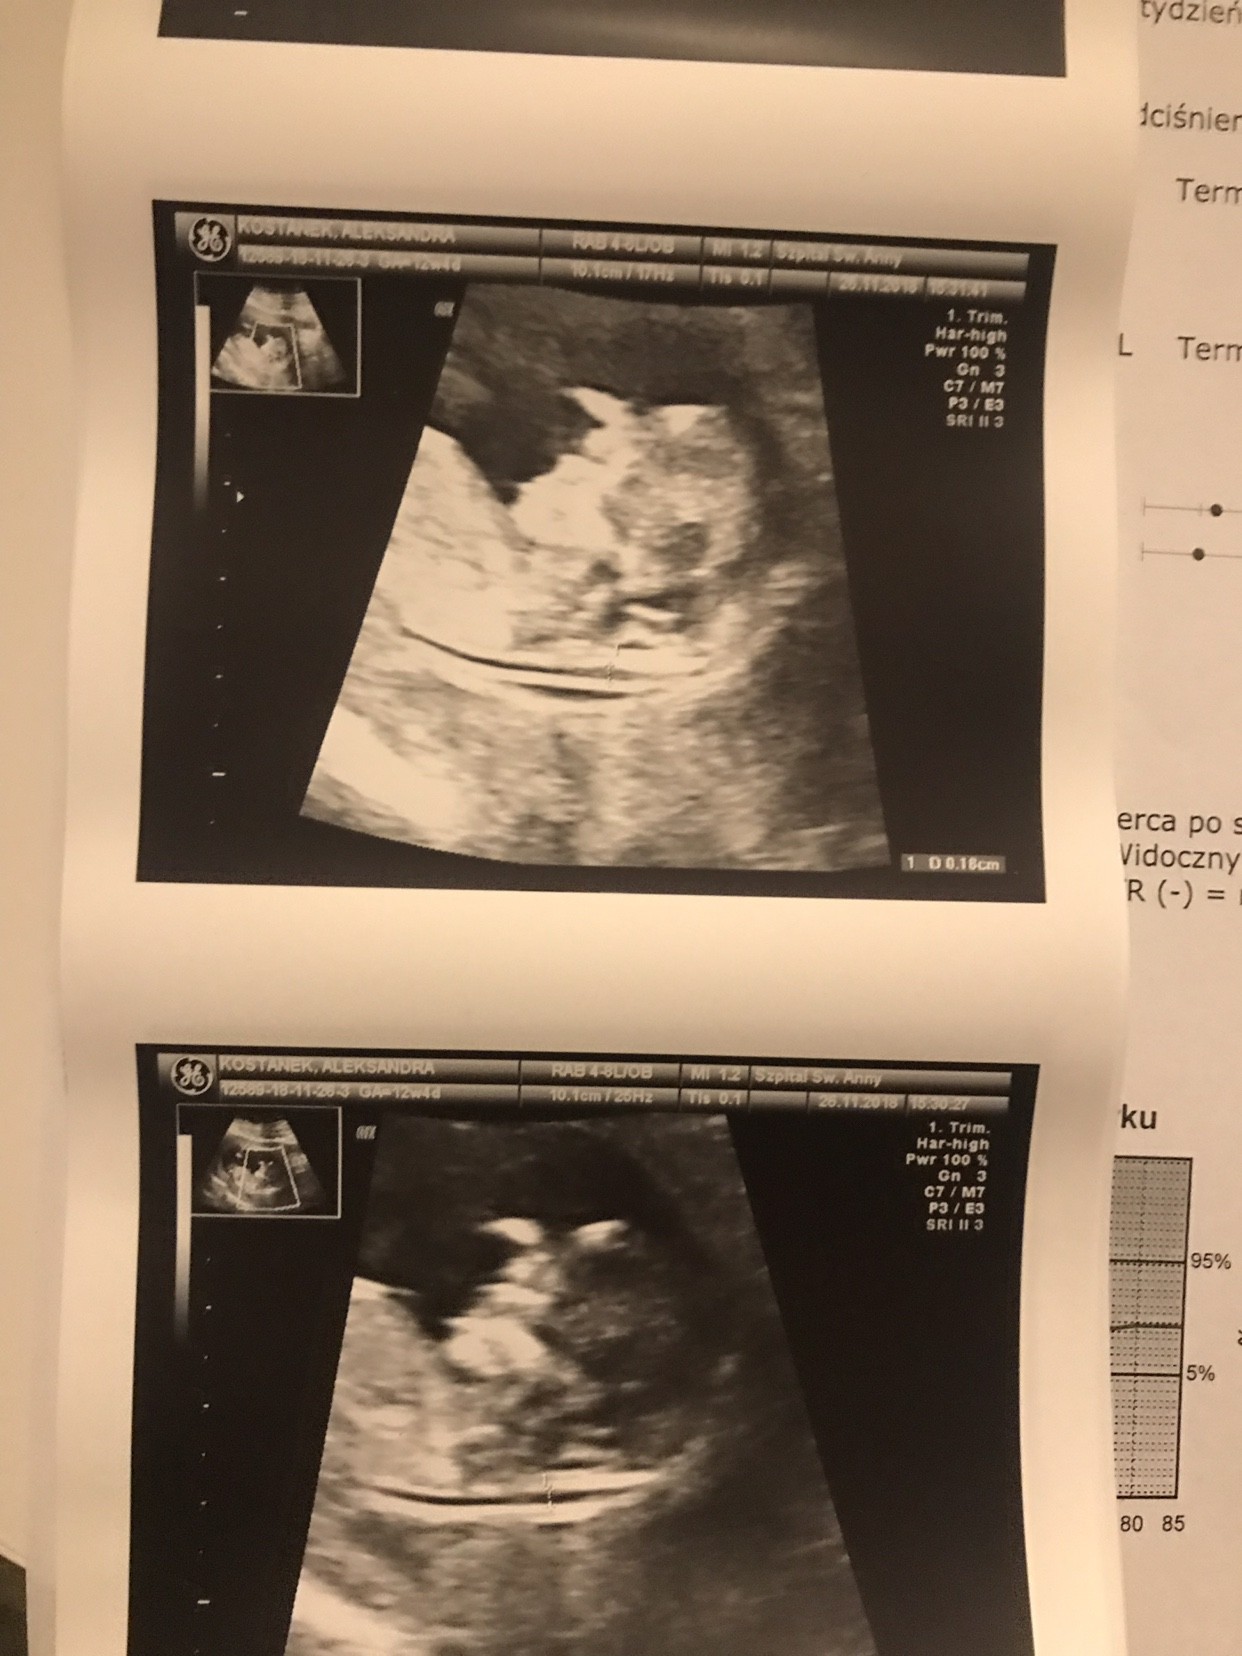

Ale cudo:* cieszę się ze wszystko okJa też już po! Wszystko wygląda dobrze, przeziernosc 1,6mm dzidzio ma 6,52cm i wszystko na swoim miejscu płeć nieznanawyniki testu krwi za tydzień. Data porodu to 05.06.